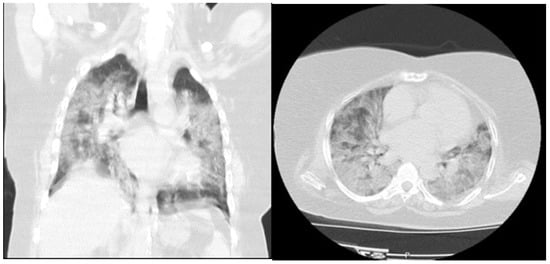

| Chest Computed Tomography | ||

| Normal | 74 (21.3) | 0 |

| Mild | 95 (27.4) | 0 |

| Moderate | 138 (39.8) | 15 (20.8) |

| Severe | 40 (11.5) | 57 (79.2) |